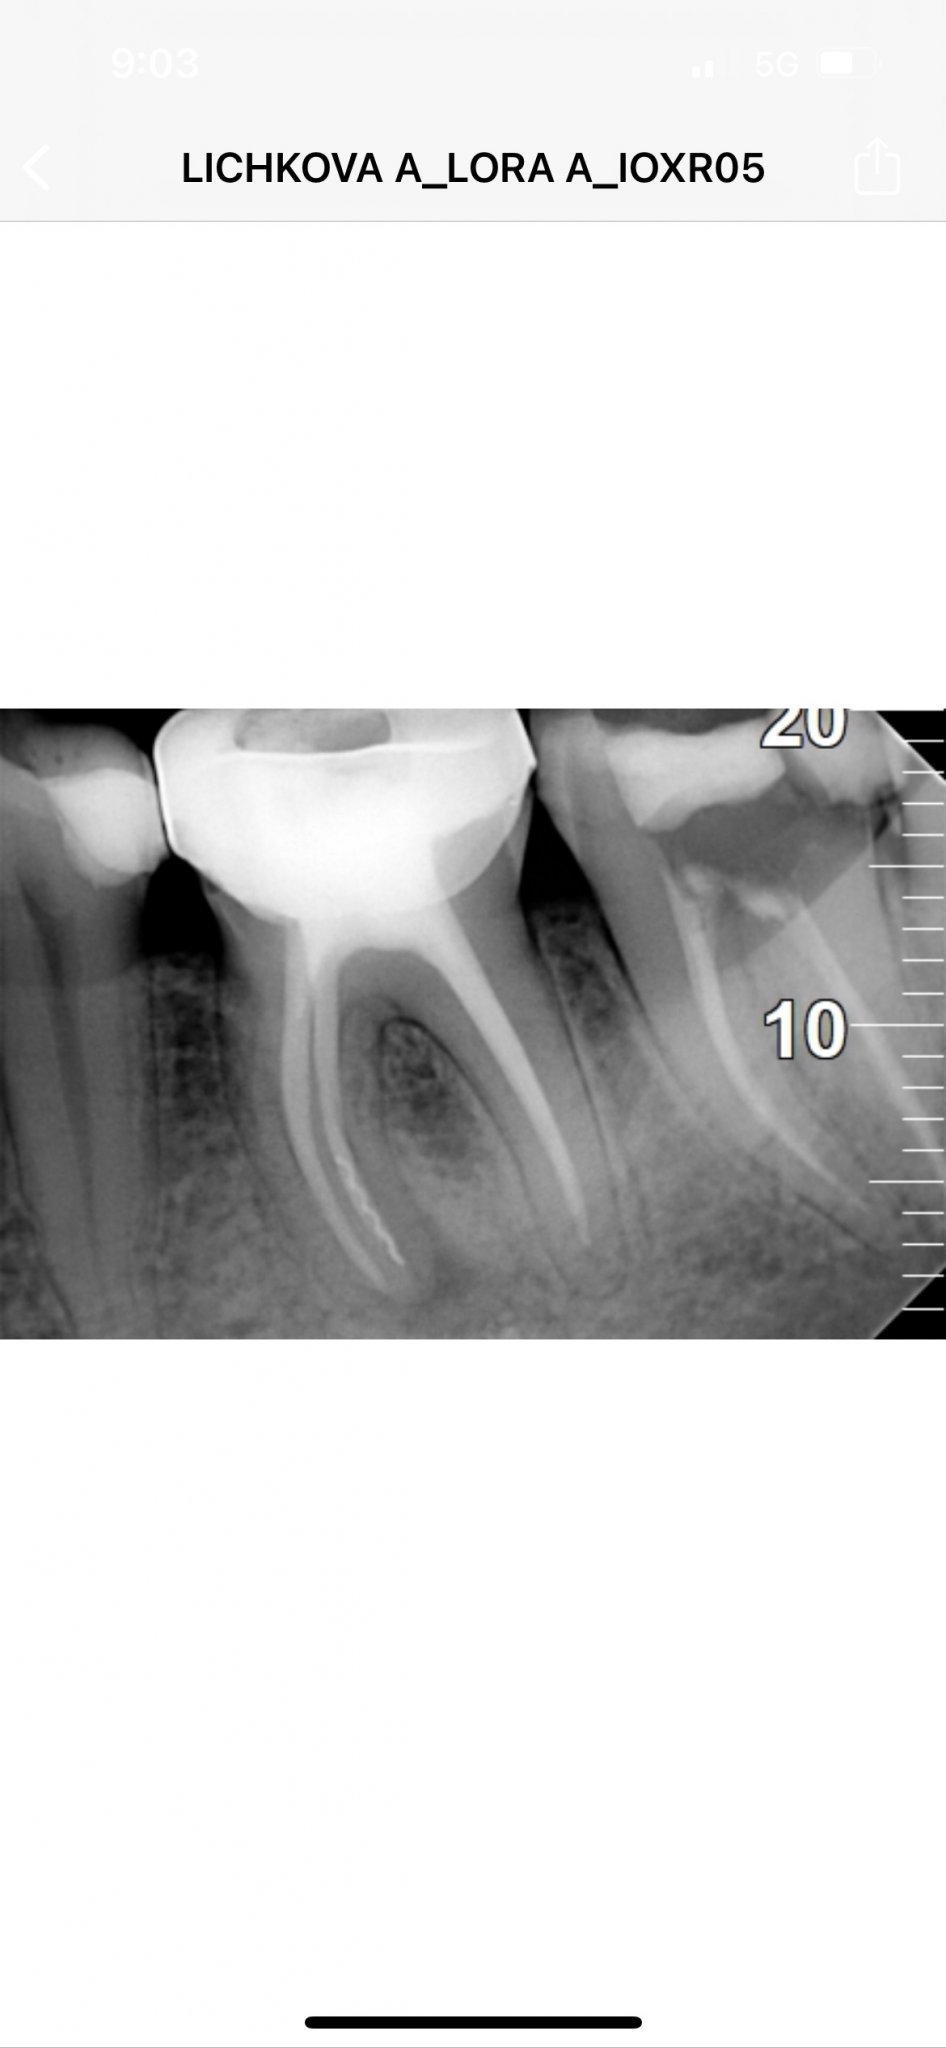

Това е снимката след като зъболекаря се опитва да извади иглата. Половината игла в извади, другата част е в канала. Запълни канала и каза, че няма да имам проблем след като е запълнен както трябва. Вече ми взеха мярка за нова корона, но аз леко се притеснявам.

delsy, не знам каква част от инструмента е извадена, но съществената е все още там. Принципно има практика инструментът да се заобиколи само и да се стигне до края на канала, в случая се вижда, че това не се е случило и притеснителното е наличието на хронично възпаление. То просто няма как да се повлияе предвид, че инстументът е там, не е заобиколен и не е стигнато до края на канала.

Освен това при такова възпаление преди да се пристъпи към постоянно възстановява е добре да се изчака около 6 месеца, за да се види, че тъканта оздравява. Иначе какво може да се случи - зъбът да не оздравее, да се обостри, да изсиква отново лечение и постоянната нова корона, която е направена да трябва да се свали и всичко отначало.

Има счупен инструмент, не до край лекуван канал (стоматологът сигурно е срещнал затруднение с проходимостта) и според мен пропусната анатомия (канал). Т.е има доста работа по този зъб.

Според мен се насочете към специалист в тази област, зъбът в момента няма рентгенологични находки на възпаление, но предвид лечението не е изключено да Ви изненада в неподходящ момент.

Ако става въпрос за София мога да Ви насоча към специалисти, ако искате ми пишете на лично.